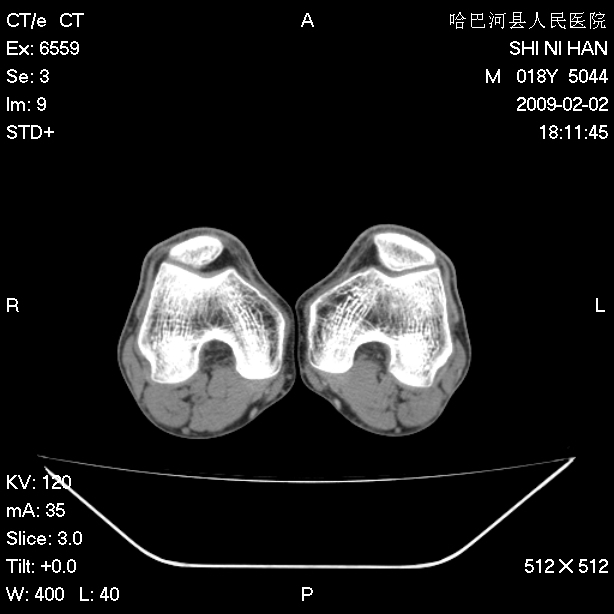

标题: CT17889:外伤后右膝关节反复疼痛3年余 [打印本页]

标题: CT17889:外伤后右膝关节反复疼痛3年余

ct未见明显异常。关节腔未见明显积液,半月板未见明显撕裂。但最好还是mri看看韧带及半月板情况。